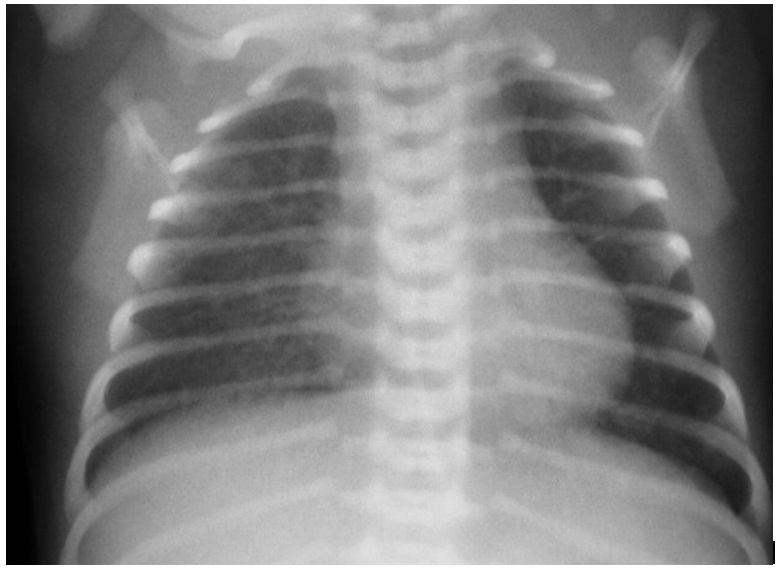

Figure 1: Chest radiograph of C. trachomatis pneumonia.

A chest radiograph of an infant with C. trachomatis pneumonia which revealed interstitial pneumonitis. Streaky shadow and reticulogranular infiltrates over the whole lung without hyperinflation were recognized.